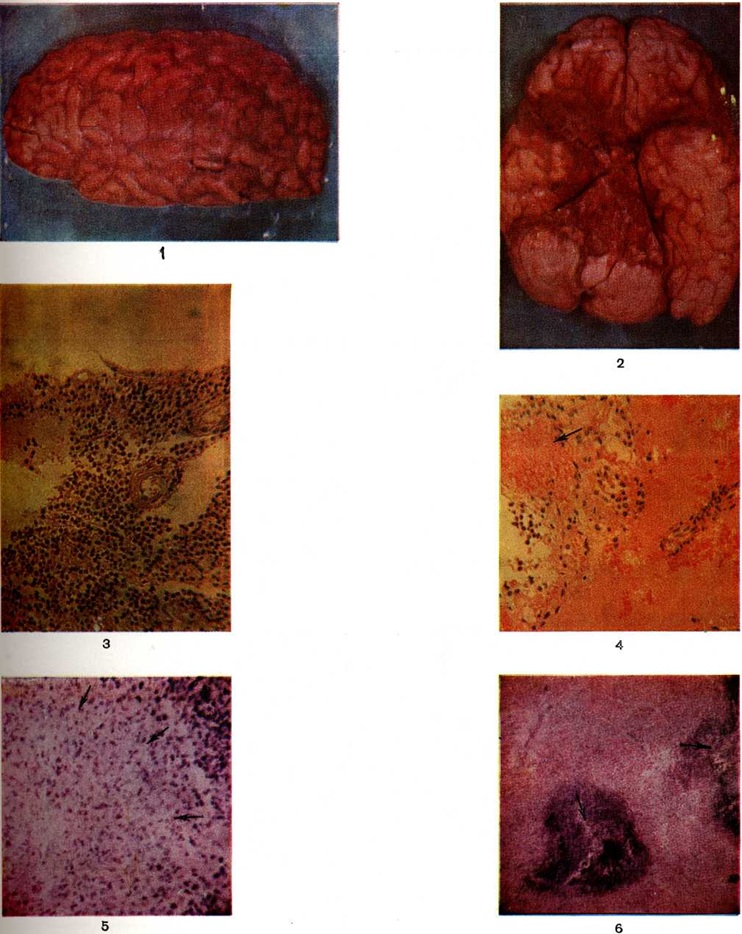

Рис. 1. Головной мозг больного, погибшего от серозного лептоменингита: гиперемия оболочек мозга с наличием экссудата в бороздах боковой поверхности полушария.

Рис. 2. Головной мозг больного, погибшего от геморрагического лептоменингита: видно обширное темно-красного цвета кровоизлияние в мягкой оболочке основания мозга.

Рис. 3—4. Микропрепараты мягкой мозговой оболочки головного мозга при пневмококковом лептоменингите.

Рис. 3. Мягкая мозговая оболочка пропитана экссудатом, в котором преобладают лимфоциты, макрофаги и плазмоциты.

Рис. 4. В отёчной, инфильтрированной лимфоцитами и лейкоцитами мягкой мозговой оболочке виден тромбированный сосуд (указан стрелкой).

Рис. 5. Микропрепарат головного мозга при туберкулёзном лептоменингите: стрелками указан участок туберкулёзной эпителиоидно-клеточной гранулемы.

Рис. 6. Микропрепарат головного мозга при туберкулёзном менингоэнцефалите: в ткани мозга видны очаги казеозного некроза (указаны стрелками).

При остром серозном лептоменингите серовато-желтоватый желатинозный экссудат скапливается в подпаутинном пространстве головного (цветной рисунок 1) и спинного мозга, обволакивая проходящие здесь крупные сосуды и нервные стволы, заполняет желудочки мозга. Мягкие оболочки, эпендима и сосудистые сплетения при этом гиперемированы, отёчны, тускловаты, с единичными или множественными кровоизлияниями. Гистологически обнаруживают картину острого серозного или серозно-фибринозного лептоменингита, эпендиматита и хориоидита (смотри полный свод знаний Хориоэпендиматит). В инфильтрате преобладают лимфоциты, макрофаги и плазмоциты (рисунок 1; и цветной рисунок 3 и 4). Воспаление носит очаговый или диффузный характер с выраженным перифокальным отёком. В связи с гиперпродукцией цереброспинальной жидкости может возникнуть острая гидроцефалия (смотри полный свод знаний), отёк и набухание головного мозга (смотри полный свод знаний) с вклинением его вещества в большое затылочное отверстие. Как правило, воспалительный выпот подвергается резорбции с полной ликвидацией патологический процесса. Однако иногда экссудат организуется, что сопровождается образованием между листками лептоменингоспаек, рассекающих подпаутинное пространство на отдельные замкнутые, переполненные цереброспинальной жидкостью полости — кисты. Микроскопически при этом обнаруживается пролиферация менинготелия и эпендимарных клеток и очаговая инфильтрация оболочек и сплетений лимфоцитами, макрофагами и плазмоцитами, а также новообразование соединительной ткани. Такая форма заболевания носит название хронический серозного или кистозного лептоменингита.

При гнойном Менингит воспалительный выпот имеет сначала серозный характер, а на 2—3-й день заболевания он приобретает вид гнойного экссудата. При этом мягкие оболочки полушарий мозга (цветной рисунок 1), сосудистые сплетения и эпендима пропитаны мутной желтовато-зеленоватой вязкой ЖИДКОСТЬЮ. При обильном накоплении гнойнофибринозный экссудат образует «чепчик» в лобной и теменной долях полушарий (цветной таблица, ст. 33, рисунок 2) или окутывает весь мозг сплошной массой. Он заполняет также мозговые полости, покрывая желтоватой плёнкой сплетения и стенки желудочков. Развивающаяся обтурация ликворных путей выпотом ведёт к острому расширению желудочков мозга (цветной рисунок 3) и церебральной гипертензии. В воспалительный процесс могут вовлекаться подоболочечные отделы мозгового вещества, но особенно часто области, окружающие желудочки.

Если в оболочечном выпоте содержатся эритроциты и, следовательно, мягкие мозговые оболочки окрашиваются в различные оттенки красного цвета, то такое воспаление этих оболочек носит название геморрагического (цветной рисунок 2). Геморрагический лептоменингит (цветной рисунок 4) может осложнить инфекционные заболевание, сопровождающееся общим тромбогеморрагическим синдромом или местной гиперергической реакцией немедленного типа. Сходную макроскопическую картину из-за примеси крови имеет реактивное воспаление в зоне субарахноидального кровоизлияния. Дифференциальной диагностике в этих случаях может помочь гистологический исследование материала — при инфекционном геморрагическом Менингит обнаруживают фибриноидные некрозы сосудов (смотри полный свод знаний Фибриноидное превращение), их тромбоз и преимущественно гранулоцитарную инфильтрацию очага воспаления.

Туберкулёзный лептоменингит — результат гематогенной генерализации или лимфогенного распространения инфекции из лёгочного, лимфожелезистого (или другого внелёгочного) очага. Современные методы лечения изменили морфологический картину заболевания. На смену острому серозно-фибринозному воспалению оболочек мозга, дававшему раньше почти 100% летальность, пришли хронический ограниченные формы поражения со значительно лучшим прогнозом. При остром туберкулёзном Менингит желатинозный серовато-желтоватый выпот обнаруживается в подпаутинном пространстве головного (цветной рисунок 5) и спинного мозга в типичных местах, а также в полостях мозга. В мягкой оболочке и в эпендиме заметны милиарные или более крупные сероватые бугорки (цветной рисунок 6). Пропитанная серозно-фибринозным выпотом ткань может подвергаться казеозному некрозу (цветной рисунок 7). Микроскопически в инфильтрате с первых же дней заболевания преобладают лимфоциты.